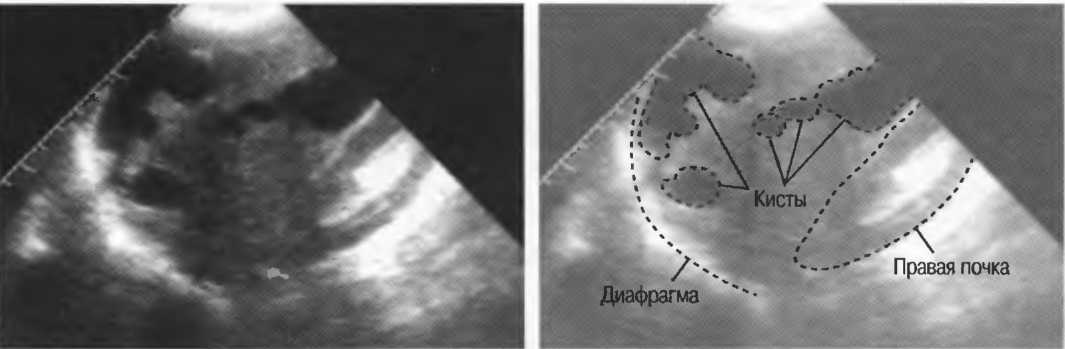

Кисты

Киста, как правило, визуализируется в виде анэхогенной зоны, при этом структуры, расположенные за кистой, обычно усилены: полость кисты анэхогенна, поскольку в ней нет структур с различным акустическим сопротивлением. В результате того что жидкость не поглощает ультразвук в такой же степени, что и ткань, эхо-сигналы от расположенных позади кисты структур гиперкомпенсированы сканером и выглядят усиленными — появляется эффект усиления задней стенки (рис. 14а,б).

Киста определяется в виде анэхогенной зоны с усилением по задней стенке. Если в кисте есть внутренние зхоструктуры, то они могут быть реальными или являться артефактами.

Артефакты могут определяться в любой кистозной структуре (такой, например, как мочевой пузырь или желчный пузырь) и чаще определяются ближе кпереди, становясь менее выраженными на глубине. Они исчезают или меняют свой характер при изменении положения датчика. Но истинные структуры в кисте, такие как перегородки, сохраняют свое местоположение независимо от положения датчика. Истинные отражения имеют место при наличии сгустка крови, гноя, некротической взвеси, и все это чаще визуализируется по задней стенке: если эти структуры не фиксированы к стенке, они изменяют свое положение при перемене положения тела пациента (рис. 16).